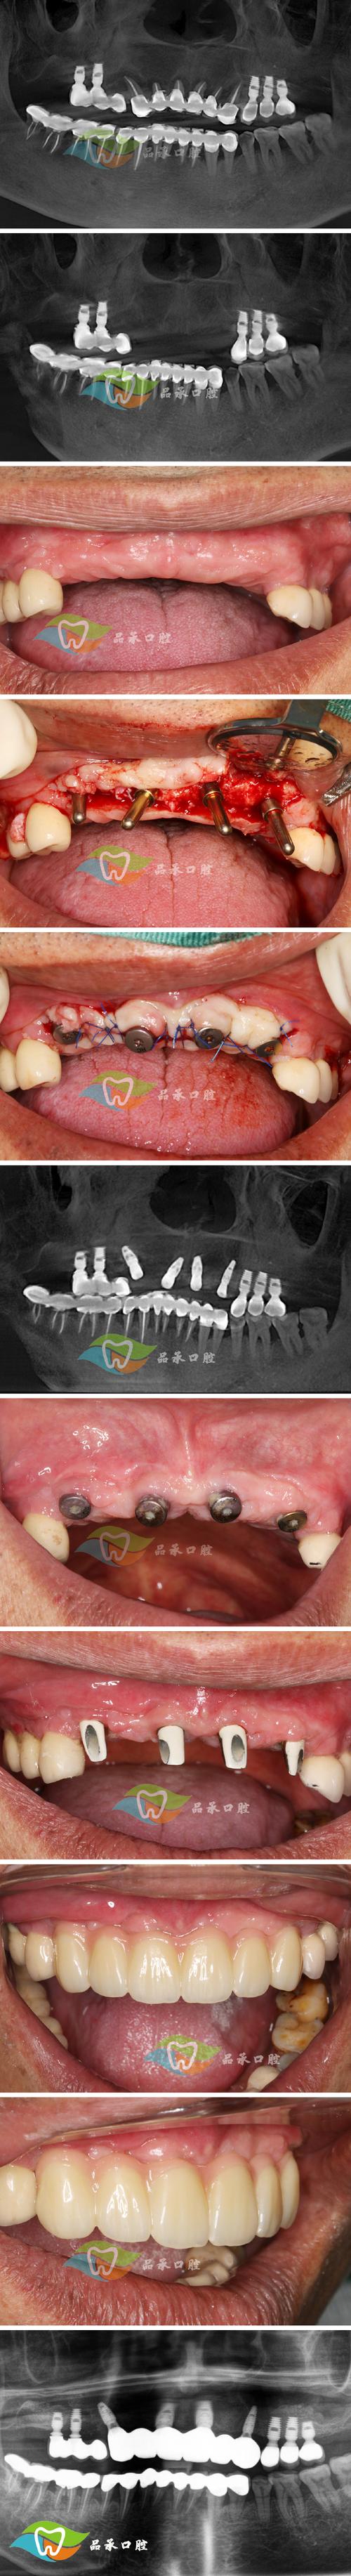

骨移植种植牙的典型流程

- 术前评估:通过CBCT测量骨缺损量,排除全身禁忌症(如未控制的糖尿病、严重骨质疏松、凝血功能障碍等)。

- 骨移植手术:在局部麻醉下切开牙龈,暴露骨缺损区,根据缺损大小选择骨移植材料(如异种骨+自体骨混合植入),覆盖可吸收胶原膜(屏障膜,防止软组织长入骨缺损区),分层缝合牙龈。

- 愈合期:骨移植材料需3-6个月与自身骨结合(自体骨3-4个月,异种骨/人工骨需6个月以上),期间定期复查(术后1、3、6个月),评估骨愈合情况。

- 二期种植手术:确认骨量充足、骨密度良好后,再次切开牙龈,植入种植体,3-6个月待种植体与骨结合后,安装基台与牙冠,完成种植修复。